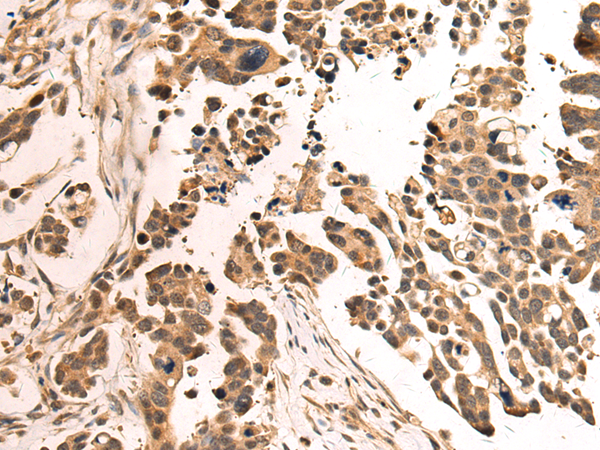

IHC positive control: |

Human prostate cancer and Human colorectal cancer |